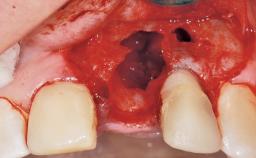

Immediate Flapless Placement of an Implant in a Maxillary Left Central Incisor Site

A 29-year-old female patient presented for treatment to replace the upper left central incisor tooth with an implant- supported restoration. The tooth had been intermittently symptomatic for the previous 12 months. The tooth had originally suffered trauma about 15 years previously. Several endodontic treatments had been performed, including an apicectomy procedure to retain the tooth. The patient was healthy and a non-smoker. She had reasonable expectations in regard to esthetic outcomes and the risk of marginal tissue recession following treatment. At medium smile, the gingival margins of the upper teeth were visible, with a display of 3 to 4 mm of the gingival margins. Gingival recession of tooth 21 and a discrepancy in the gingival levels between teeth 11 and 21 was observable during normal speech and smile.

Socket Integrity Damage to one or more bone walls

Bone Volume Damage to one or more socket walls

Esthetic Risk Medium